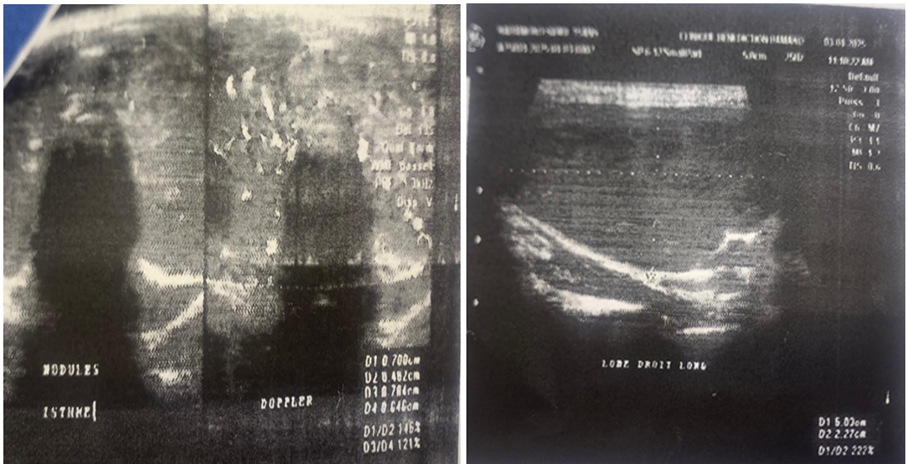

Figure 2: Thyroid ultrasound of the patient (As a clue by the arrows, 2 very vascularized isthmic nodules ; on a heterogeneous and hypervascularized goiter).

Cervical ultrasound (Figure 2) revealed the following :

- An enlarged right lobe, echogenic, heterogeneous, and measuring 50x26x21mm

- An enlarged left lobe, measuring 50x26x23mm, echogenic and heterogeneous

- Isthmic hypertrophy (11mm thick), grossly echogenic, heterogeneous, and presenting two nodules measuring 07x06mm and 07x04mm

- No cervical lymphadenopathy, and the jugulocarotid bundles appeared normal

- On color Doppler, diffuse and perinodular hypervascularization of the thyroid gland related to thyroid overactivity